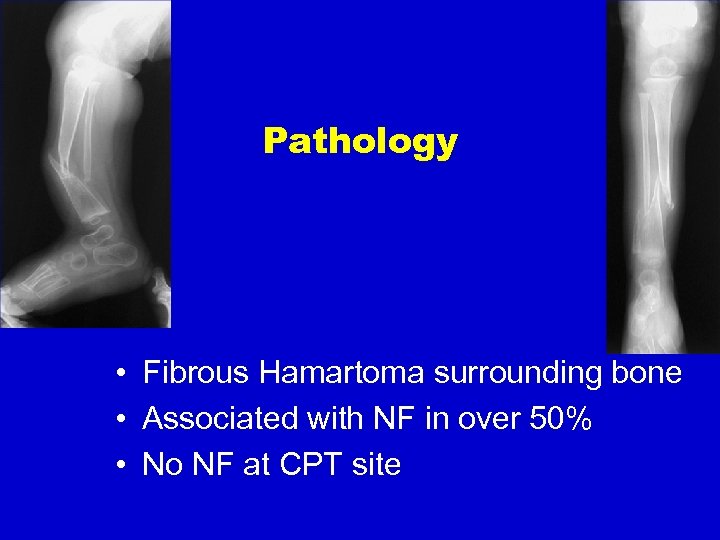

Pathology • Fibrous Hamartoma surrounding bone • Associated with NF in over 50% • No NF at CPT site